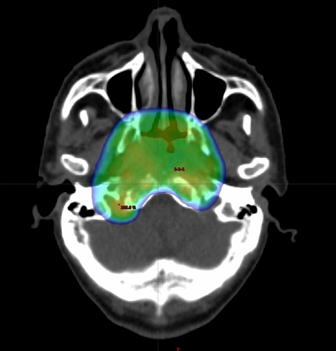

治療計画の様子

上咽頭癌に対するVMAT